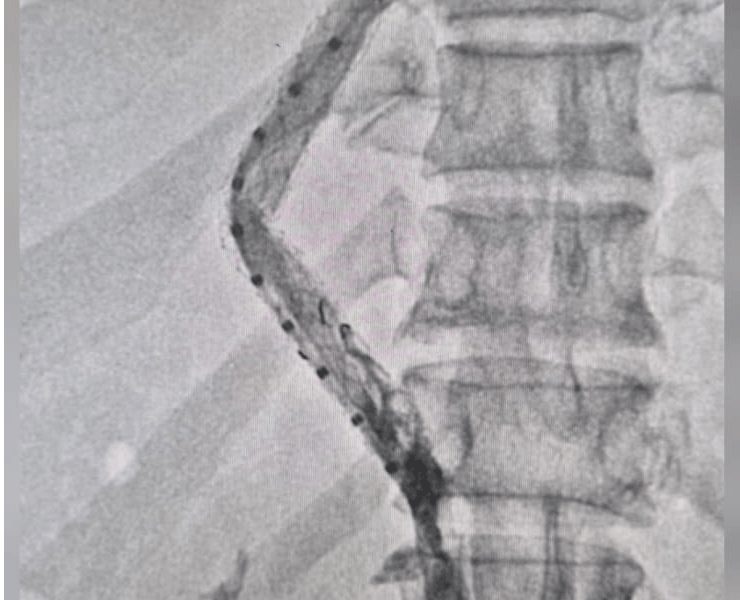

TIPS and DIPS are performed in a specialised catheterisation lab under ultrasound and fluoroscopy (X‑ray) guidance, usually through a vein in the neck (internal jugular vein).

- Transjugular access: a thin catheter is passed from the neck vein into the hepatic or IVC system.

- Portal vein puncture: the right portal vein branch is carefully punctured from inside the liver.

Before and after procedure, we did DIPS procedure on this patient